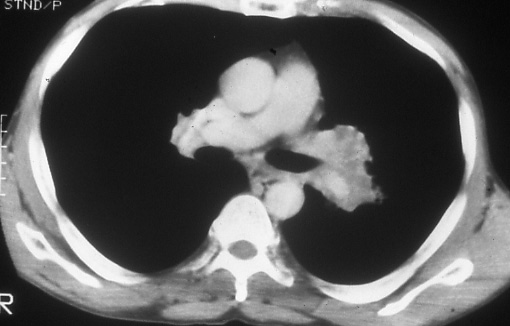

Fig.

23: Computed

tomographic scan of the

chest shows extensive

left hilar adenopathy

in a patient with a left

upper lobe bronchogenic

carcinoma, N1 disease. |